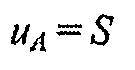

6.3. Стандартную неопределенность, обусловленную источниками, имеющими случайный характер, %, принимают равной среднему квадратическому отклонению S, %, рассчитанному по формулам (5) или (6):

(7)